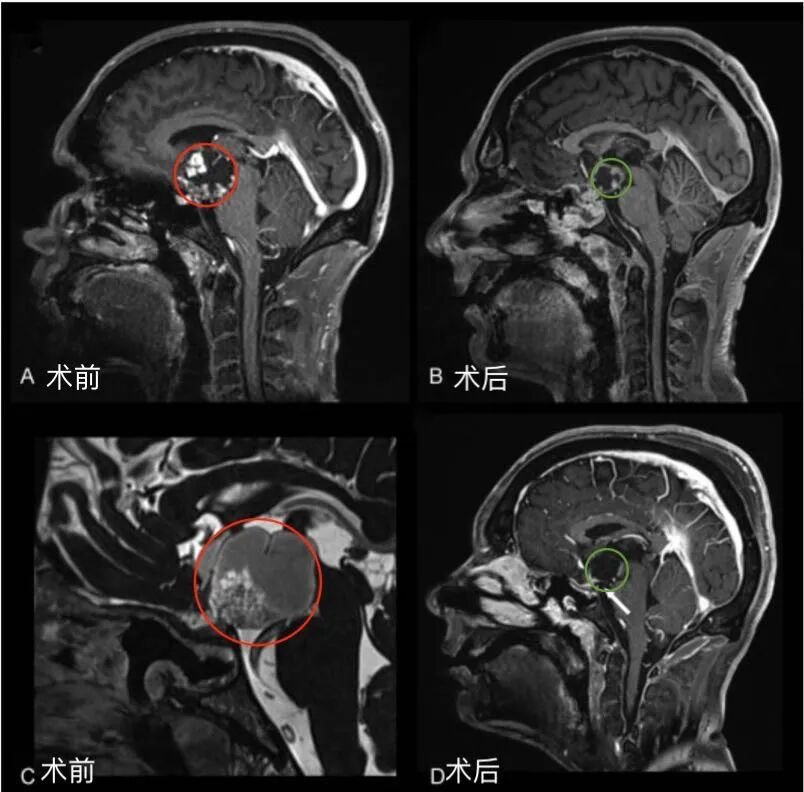

第一阶段,采用经神经内镜经鼻入路,对视交叉和神经进行减压,为后续处理奠定基础。然而随着肿瘤加速生长,新的视觉缺损相继出现,对下丘脑和第三脑室的压迫持续加重,需要再次手术切除。第二阶段,经后岩骨入路(即后迷路经天幕入路)可充分暴露肿瘤及周围解剖结构,包括第三脑室底部及侧壁、分支血管、视神经等。

手术过程中详细处理了后岩骨入路的相关技术要点及术中解剖细节,涵盖横窦-乙状窦连接部的后方移位、天幕切开时静脉结构的保护方式、肿瘤切除过程中第三脑室底部的辨认与保护,以及精细的多层次缝合关闭等步骤。

术后情况

术后威尔视力、视野均恢复正常,无颅神经麻痹症状,认知功能明显改善,垂体功能亦恢复至正常水平。